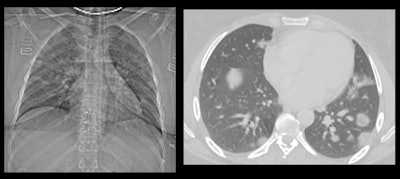

"This was a male patient in his 60s who was admitted to hospital in March 2020 with fever and shortness of breath. I was asked for my opinion on the x-ray by a respiratory physician, and as soon as I looked at it, my initial reaction was: 'Oh, wow, what am I looking at here?' It looked very unusual compared to what I would usually expect to see in a standard chest infection," he said.

Hare only recognized the image as COVID-19 because it was very similar to cases that he had been reading about in medical journals. He felt particularly proud of the interpretation of the x-ray by a radiologist because it informed the clinicians that this was a COVID-19 diagnosis -- despite the patient having a negative COVID-19 swab test. "That's very important because it shows the powerful role of imaging in determining fever in patients. Now we often get asked what a COVID lung actually looks like."